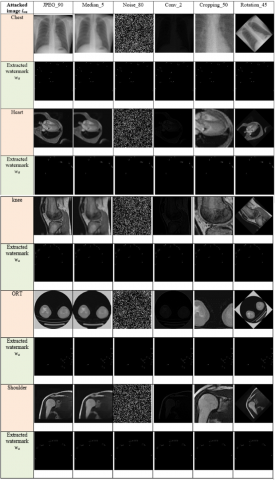

A number of attacks have been applied on different watermarked images including geometric and non-geometric attacks using one of the well-known benchmarks in the field of watermarking called Stirmark benchmark [17] such JPEG compression, Filtering by median, adding noise, convolution, cropping and rotation. These attacks aim to influence the watermark through the watermarked image and then make its extraction difficult. Figure 8 shows some attacks on a sample of watermarked images.

Figure 8. Example of attacks on watermarked images

Figure 9 shows the extracted watermarks from the different host images for each attack.

Figure 9. Watermarks extraction phase